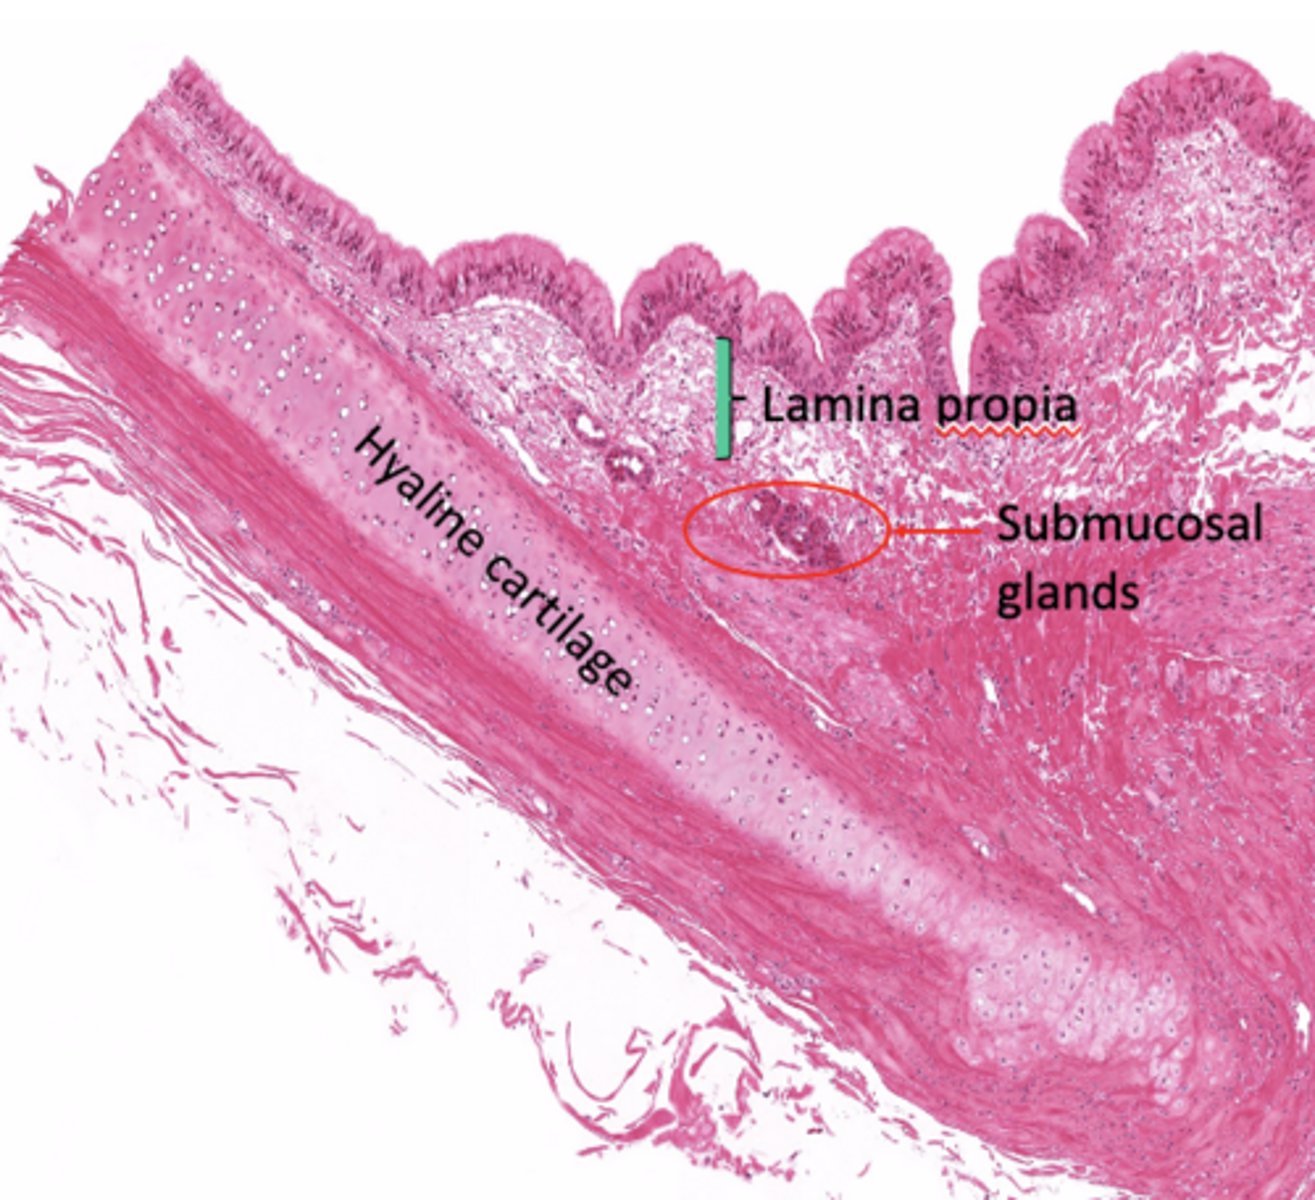

What layers make up the trachea?

Mucosa, submucosa, cartilaginous layer, adventitia.

What is characteristic of the lamina propria in the trachea?

What does the submucosa contain?

Dense irregular CT and glandular elements.

What type of cartilage supports the trachea?

Hyaline cartilage (16-20 C shaped rings)